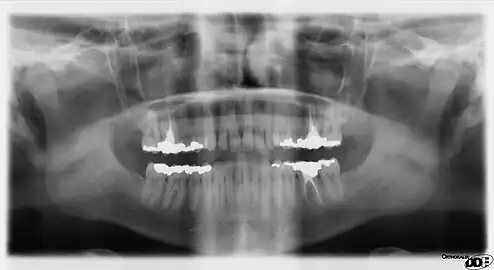

Dental radiographs, commonly known as X-rays, are radiographs used to diagnose hidden dental structures, malignant or benign masses, bone loss, and cavities.

A radiographic image is formed by a controlled burst of X-ray radiation which penetrates oral structures at different levels, depending on varying anatomical densities, before striking the film or sensor. Teeth appear lighter because less radiation penetrates them to reach the film. Dental caries, infections and other changes in the bone density, and the periodontal ligament, appear darker because X-rays readily penetrate these less dense structures. Dental restorations (fillings, crowns) may appear lighter or darker, depending on the density of the material.

It is possible for both tooth decay and periodontal disease to be missed during a clinical exam, and radiographic evaluation of the dental and periodontal tissues is a critical segment of the comprehensive oral examination. The photographic montage at right depicts a situation in which extensive decay had been overlooked by a number of dentists prior to radiographic evaluation.